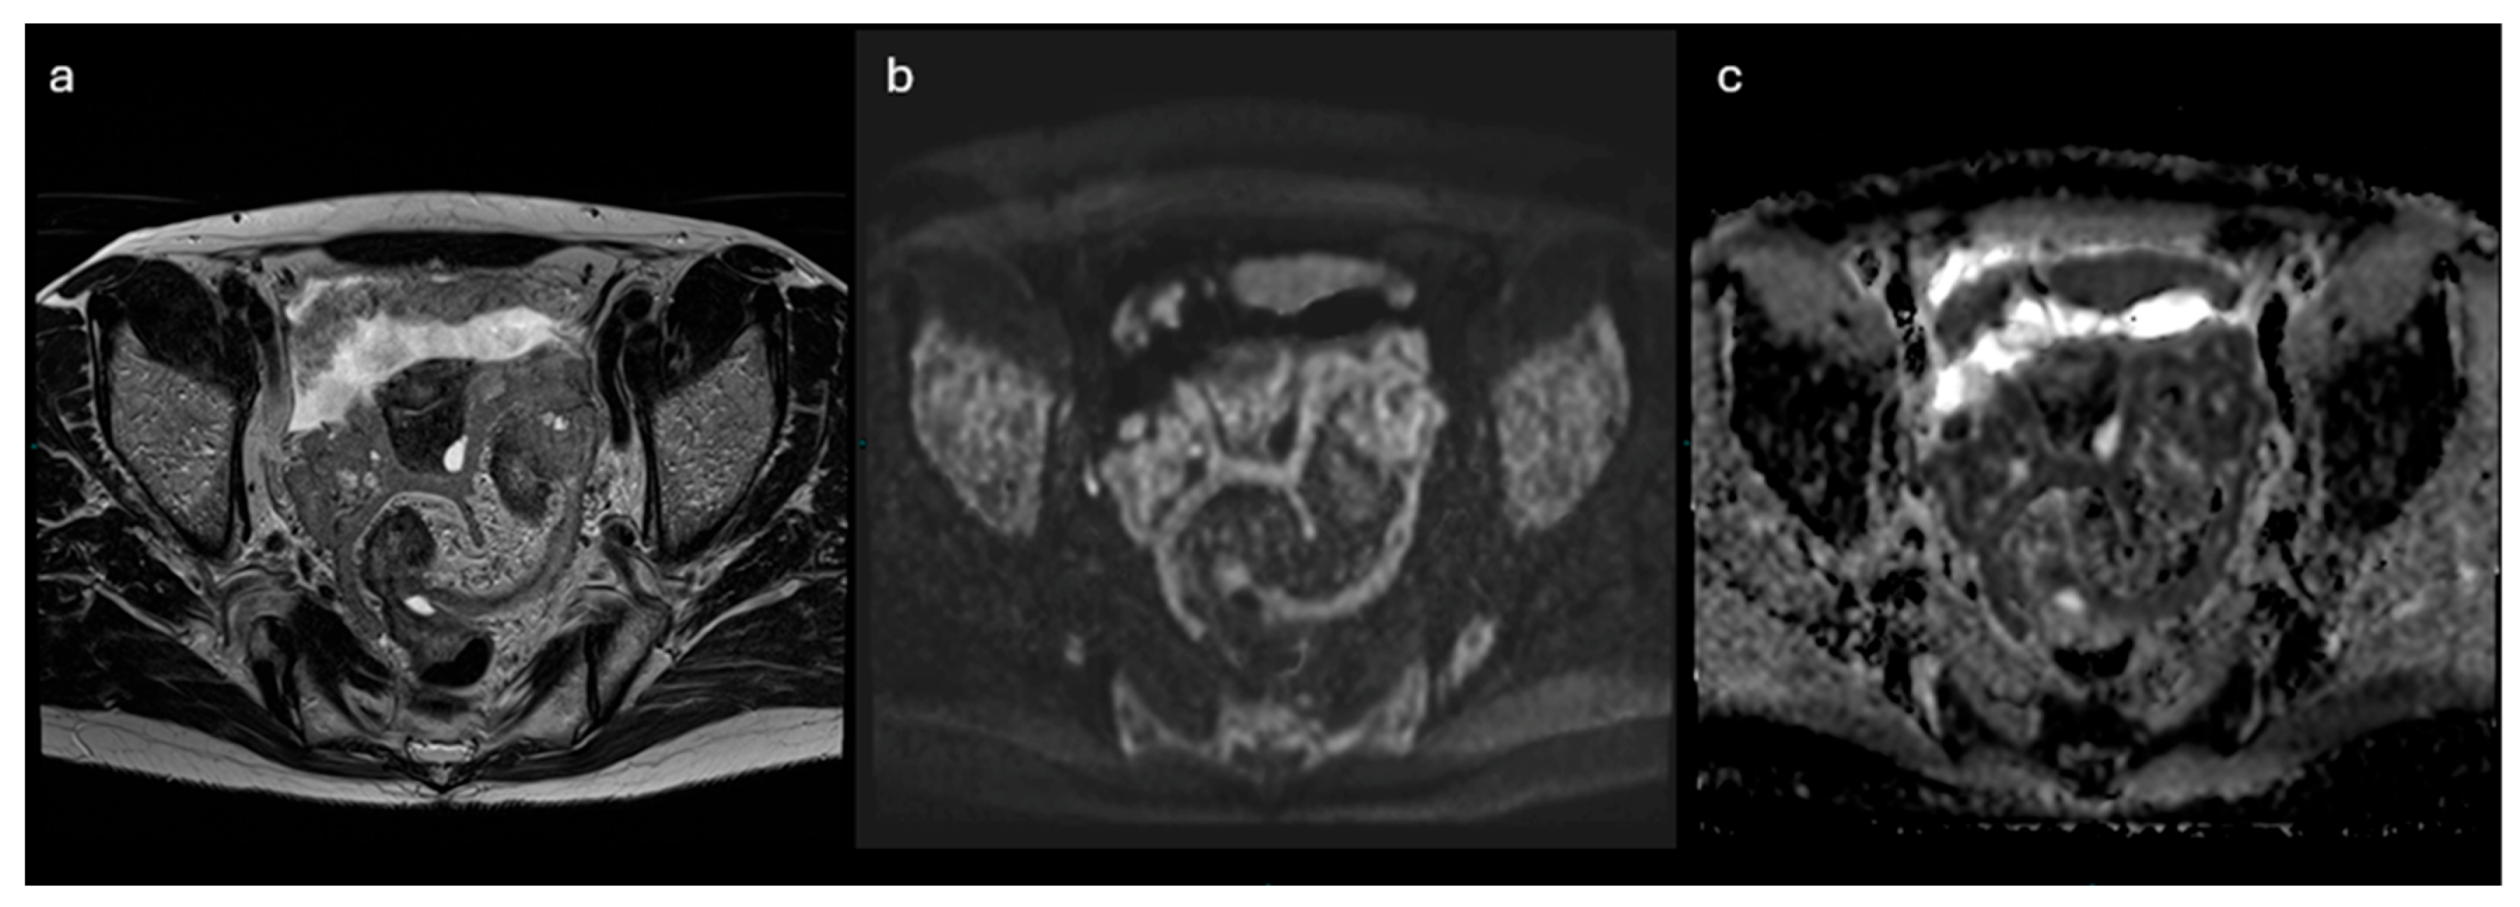

3.2. NON- CONTRAST- MRI Score

| Non-contrast MRI score | Definition | MRI features |

|---|---|---|

| Score 1 | No mass | No adnexal mass is demonstrated in pelvic MRI study |

| Score 2 | Benign/likely benign | Radiologically characterized with radiological diagnosis (e.g. endometrioma, dermoid, fibroma) |

| Score 3 | Indeterminate | Not classified in other scores; it may have a solid appearing component without reaching criteria for “solid tissue” |

| Score 4 | Suspicious for malignancy | Solid tissue criteria reached |

| Score 5 | Highly suspicious for malignancy | Solid tissue criteria reached and presence of - Peritoneal implants - Lymphadenopathy and/or - Ascites in the presence of solid tissue, after benign diagnoses are excluded |